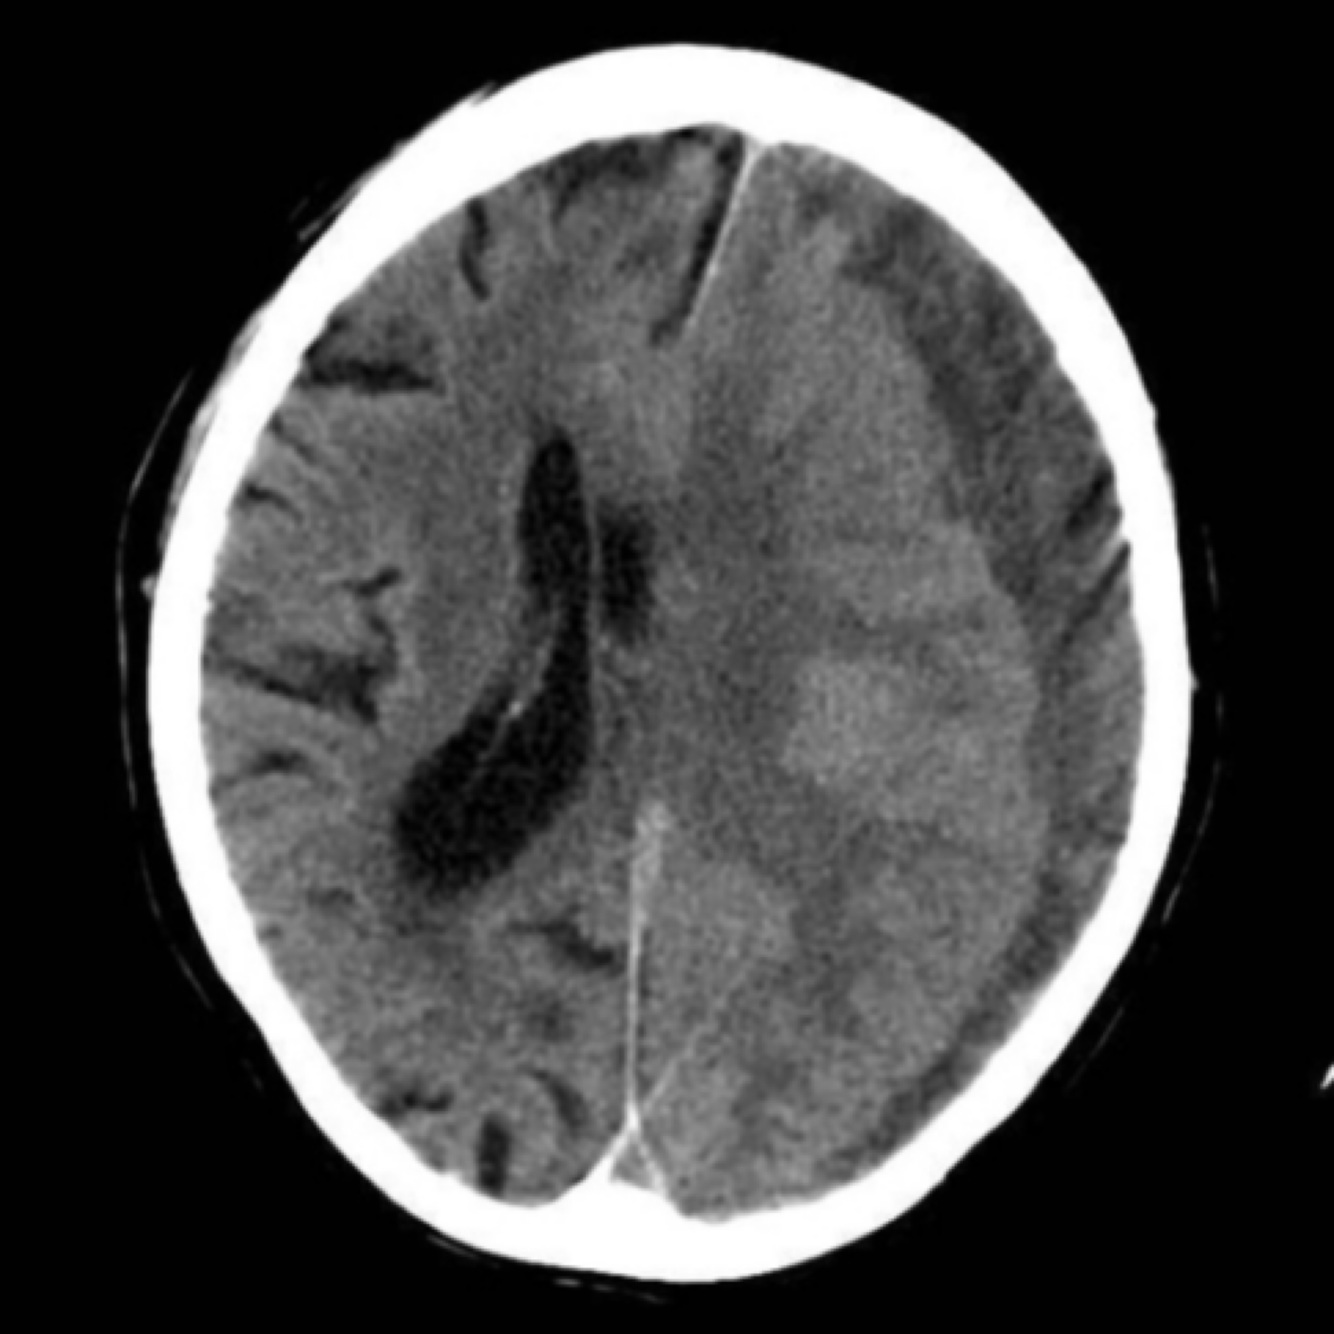

What may be seen on CT in an SAH?

Blood will cause hyperattenuation in the subarachnoid space.

Subarachnoid haemorrhage